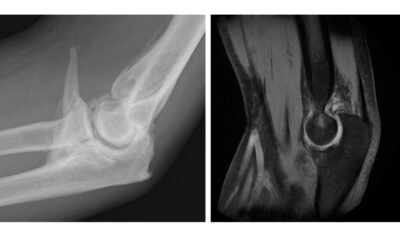

Fracturas  y fracturas luxaciones de codo.

En personas sanas, los huesos y la articulación del codo pueden romperse a consecuencia de traumatismos desde la propia altura o con golpes de más alta energía, como caídas de altura, accidentes deportivos como caídas en bici o patines, o en accidentes en vehículos a...